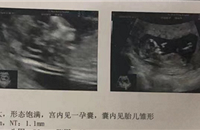

糖耐和三维临近国庆了,抓紧时间先做了糖耐,检查前一天晚上8点以后禁食禁水,我之前建档的时候空腹血糖就有一点点超,生怕过不了,前两三天就开始控制饮食了。到医院先空腹抽血,然后拿葡萄糖水,找到导医台处,加点水就可以了。5分钟内要喝完,能一口喝的孕妈应该会感到很幸福。这糖水,真的齁甜,齁喉咙的那种,我喝第一口就感觉喉咙不舒服,分了好几口才喝下去。